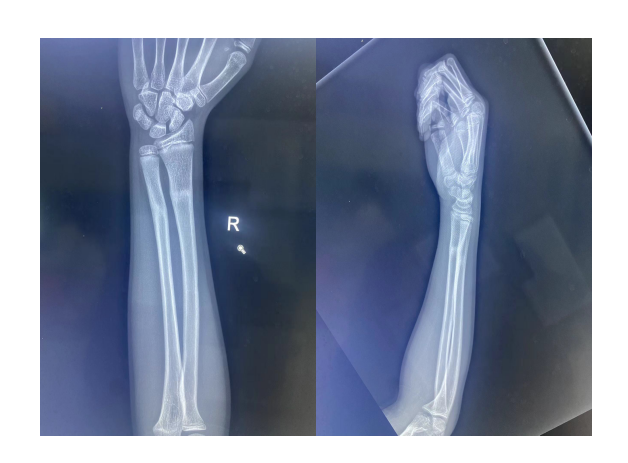

出院后复查,X片显示已基本恢复如初。